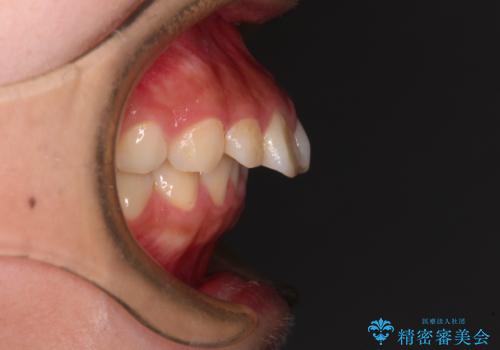

- 飛び出した上顎前歯と、閉じにくい唇、口元の突出した印象の横顔を気にして来院された患者様です。

骨格的な上顎前突であり、上下前歯の前後的な距離が大きいため、上顎は左右第一小臼歯を、下顎は左右第二小臼歯をそれぞれ2本抜歯することで前歯が接触するようにし、さらには奥歯の咬み合わせも、より理想的な状態へ近づけていくこととしました。